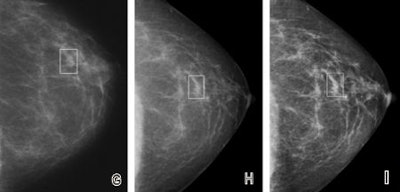

![]() |

| Fatty breast depicted on (A, D, G) film-screen and (B, C, E, F, H, I) digital left mammograms obtained in 53-year-old woman. Cancerous areas are outlined in rectangles. (A-F) Mediolateral oblique and (G-I) craniocaudal views are shown. The cancer, a mass that proved to be an invasive ductal carcinoma, is much more apparent on the film-screen images than on the digital images, with visibility being greatest on the film-screen mediolateral oblique views. The difference in lesion visibility between the film-screen and digital mammograms is accentuated when the film-screen overview image (A) is compared with the digital overview image obtained by using the default image processing algorithm (B). Close-up views of cancerous areas outlined in A (D) and B (E) are shown. There is a slight improvement in the visibility of the lesion depicted at digital mammography performed by using the Premium View image processing software, as seen on digital mediolateral oblique overview (C), film-screen mediolateral oblique close-up view (D), and digital craniocaudal (I) images. |